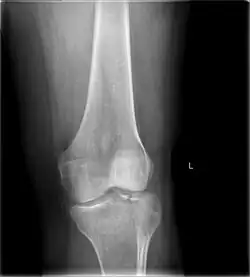

Diagnosis

In all injuries to the tibial plateau radiographs (commonly called x-rays) are imperative. Computed tomography scans are not always necessary but are sometimes critical for evaluating degree of fracture and determining a treatment plan that would not be possible with plain radiographs.[10] Magnetic Resonance images are the diagnostic modality of choice when meniscal, ligamentous and soft tissue injuries are suspected.[11][12] CT angiography should be considered if there is alteration of the distal pulses or concern about arterial injury.